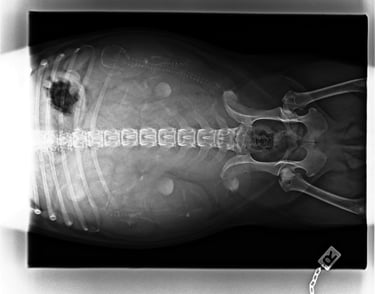

24.09.2025

58ter Trächtigkeitstag.....

Heute wurde unsere Hedi geröntgt, ihr geht es noch gut, der Countdown läuft: In zwei, drei Tagen lüftet unsere Hedi ihr Geheimnis.... Vom Röntgenbild haben wir uns mehr versprochen, aber na gut vier Welpen sind auf jeden Fall gesichtet worden..... Und wir freuen uns und sind sehr gespannt was Letzt endlich kommen wird :-))

Gewicht: 12 kg